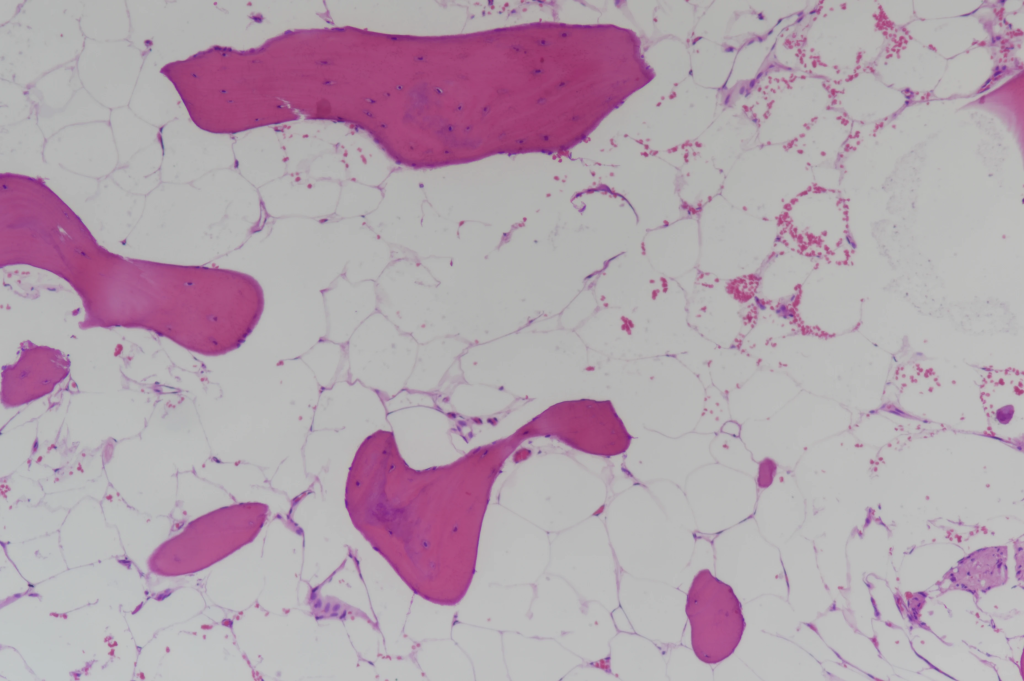

Ochronosis pathology